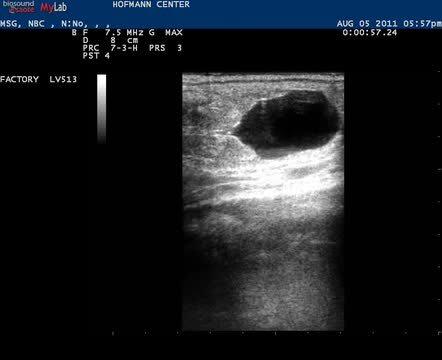

Video of Ultrasonographic Examination of the Genital Tract, Mare

This video demonstrates a thorough examination that includes careful continuous imaging of the uterine body, each uterine horn, and its ipsilateral ovary. A 22-day conceptus was imaged that precluded this mare from having a complete breeding soundness examination.

Courtesy of Maria Schnobrich.